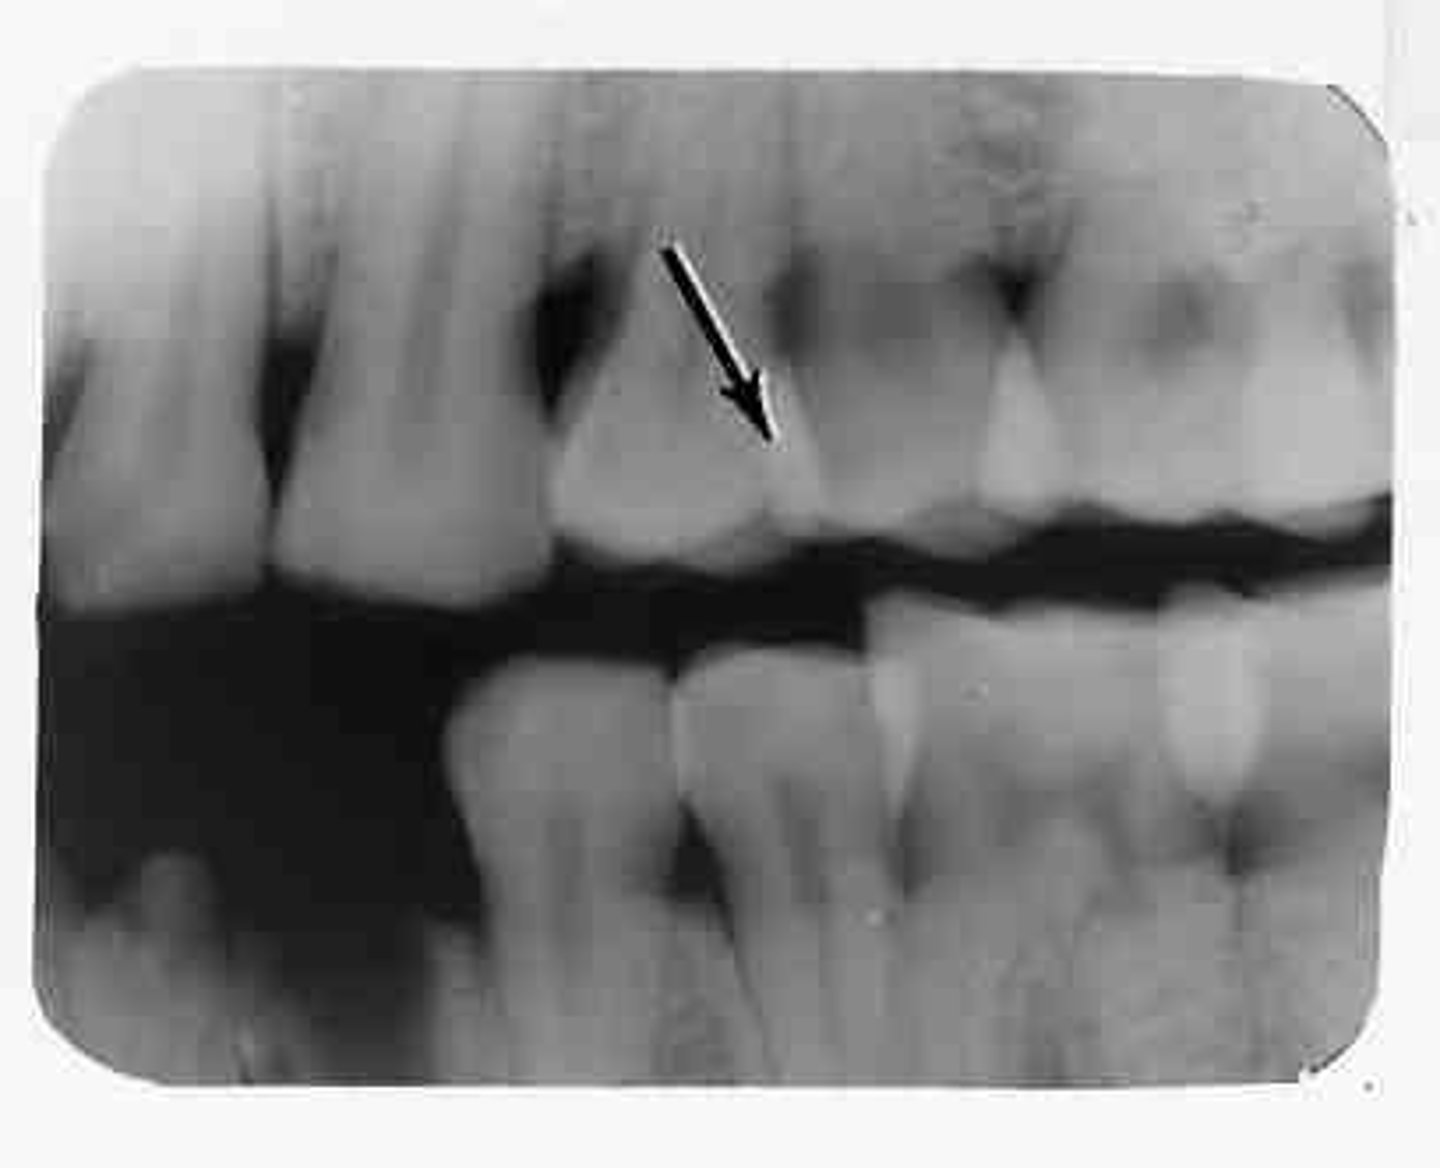

Overlapped contacts

The area where the contact area of one tooth is superimposed over the contact area of an adjacent tooth.